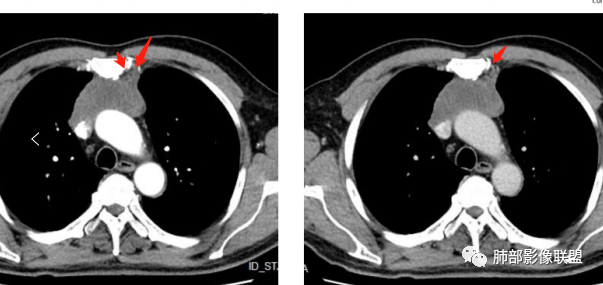

男性患者,65岁,前胸后背疼痛一个月。影像学前上纵隔分叶状的软组织肿块,肿块形态怪异,偏软,位于大血管间隙前,并有向血管后间隙发展的趋势,平扫CT值为40左右,增强扫描中心部未见强化,周围轻度的强化,约为50左右。前上纵隔的疾病谱包抬胸廓内甲状腺肿、胸腺瘤/癌、畸胎瘤、淋巴瘤。少见的心包囊肿或支气管囊肿。根据肿块的形态及强化特点,首先还是排除了胸内甲状腺肿及胸腺来源的肿物,这类的肿物强化比较明显。畸胎瘤成分比较复杂,具有软组织钙化或者脂肪类的组织,这个肿物虽然在平扫的时候好像有斑点状的钙化灶,但是总体成分还是比较单一,所以还是排除畸胎瘤的诊断。所以这样的情况是考虑:淋巴类的肿瘤,注意排除心包的囊肿或支气管来源的囊肿。

老年男性患者,前膈软组织肿块,边缘轮廓不光整,边界似乎尚清晰,内见小点状钙化灶,平扫密度欠均匀,增强后轻度强化表现,边缘有些斑片状的高强化区。综合考虑胸腺瘤或胸腺鳞癌,神经内分泌癌强化弱了一些。患者年龄较大,生殖细胞肿瘤不考虑,淋巴瘤血管包绕不够,可能性不大

前纵隔胸腺区分叶状软组织肿块影,轻度不均匀强化,中心可见坏死,边缘不清,病灶与邻近心包见条索影,上腔静脉受侵,上纵隔多发小淋巴结,考虑胸腺鳞癌可能。

老年男性,前纵隔肿块,形态不规则,右侧内乳动脉增粗,与血管脂肪间隙模糊消失,定性恶性,周围多发小淋巴结,有斑点状钙化灶,增强中心低密度区无强化,边缘强化为主,首先考虑胸腺鳞癌,鉴别胸腺瘤。

中老年男性,前纵隔占位,基本居中,向两侧生长;边缘膨隆分叶,部分边界不清,增强不均匀轻中度强化,坏死区边界不清;周围多发增大淋巴结,考虑恶性。主要在胸腺癌、胸腺瘤、淋巴瘤之间鉴别。病灶偏软,有钻缝样生长,这些征象偏向于淋巴瘤。但此例老年患者,病灶内有点状钙化,缺乏结节堆砌感,倾向胸腺癌诊断。